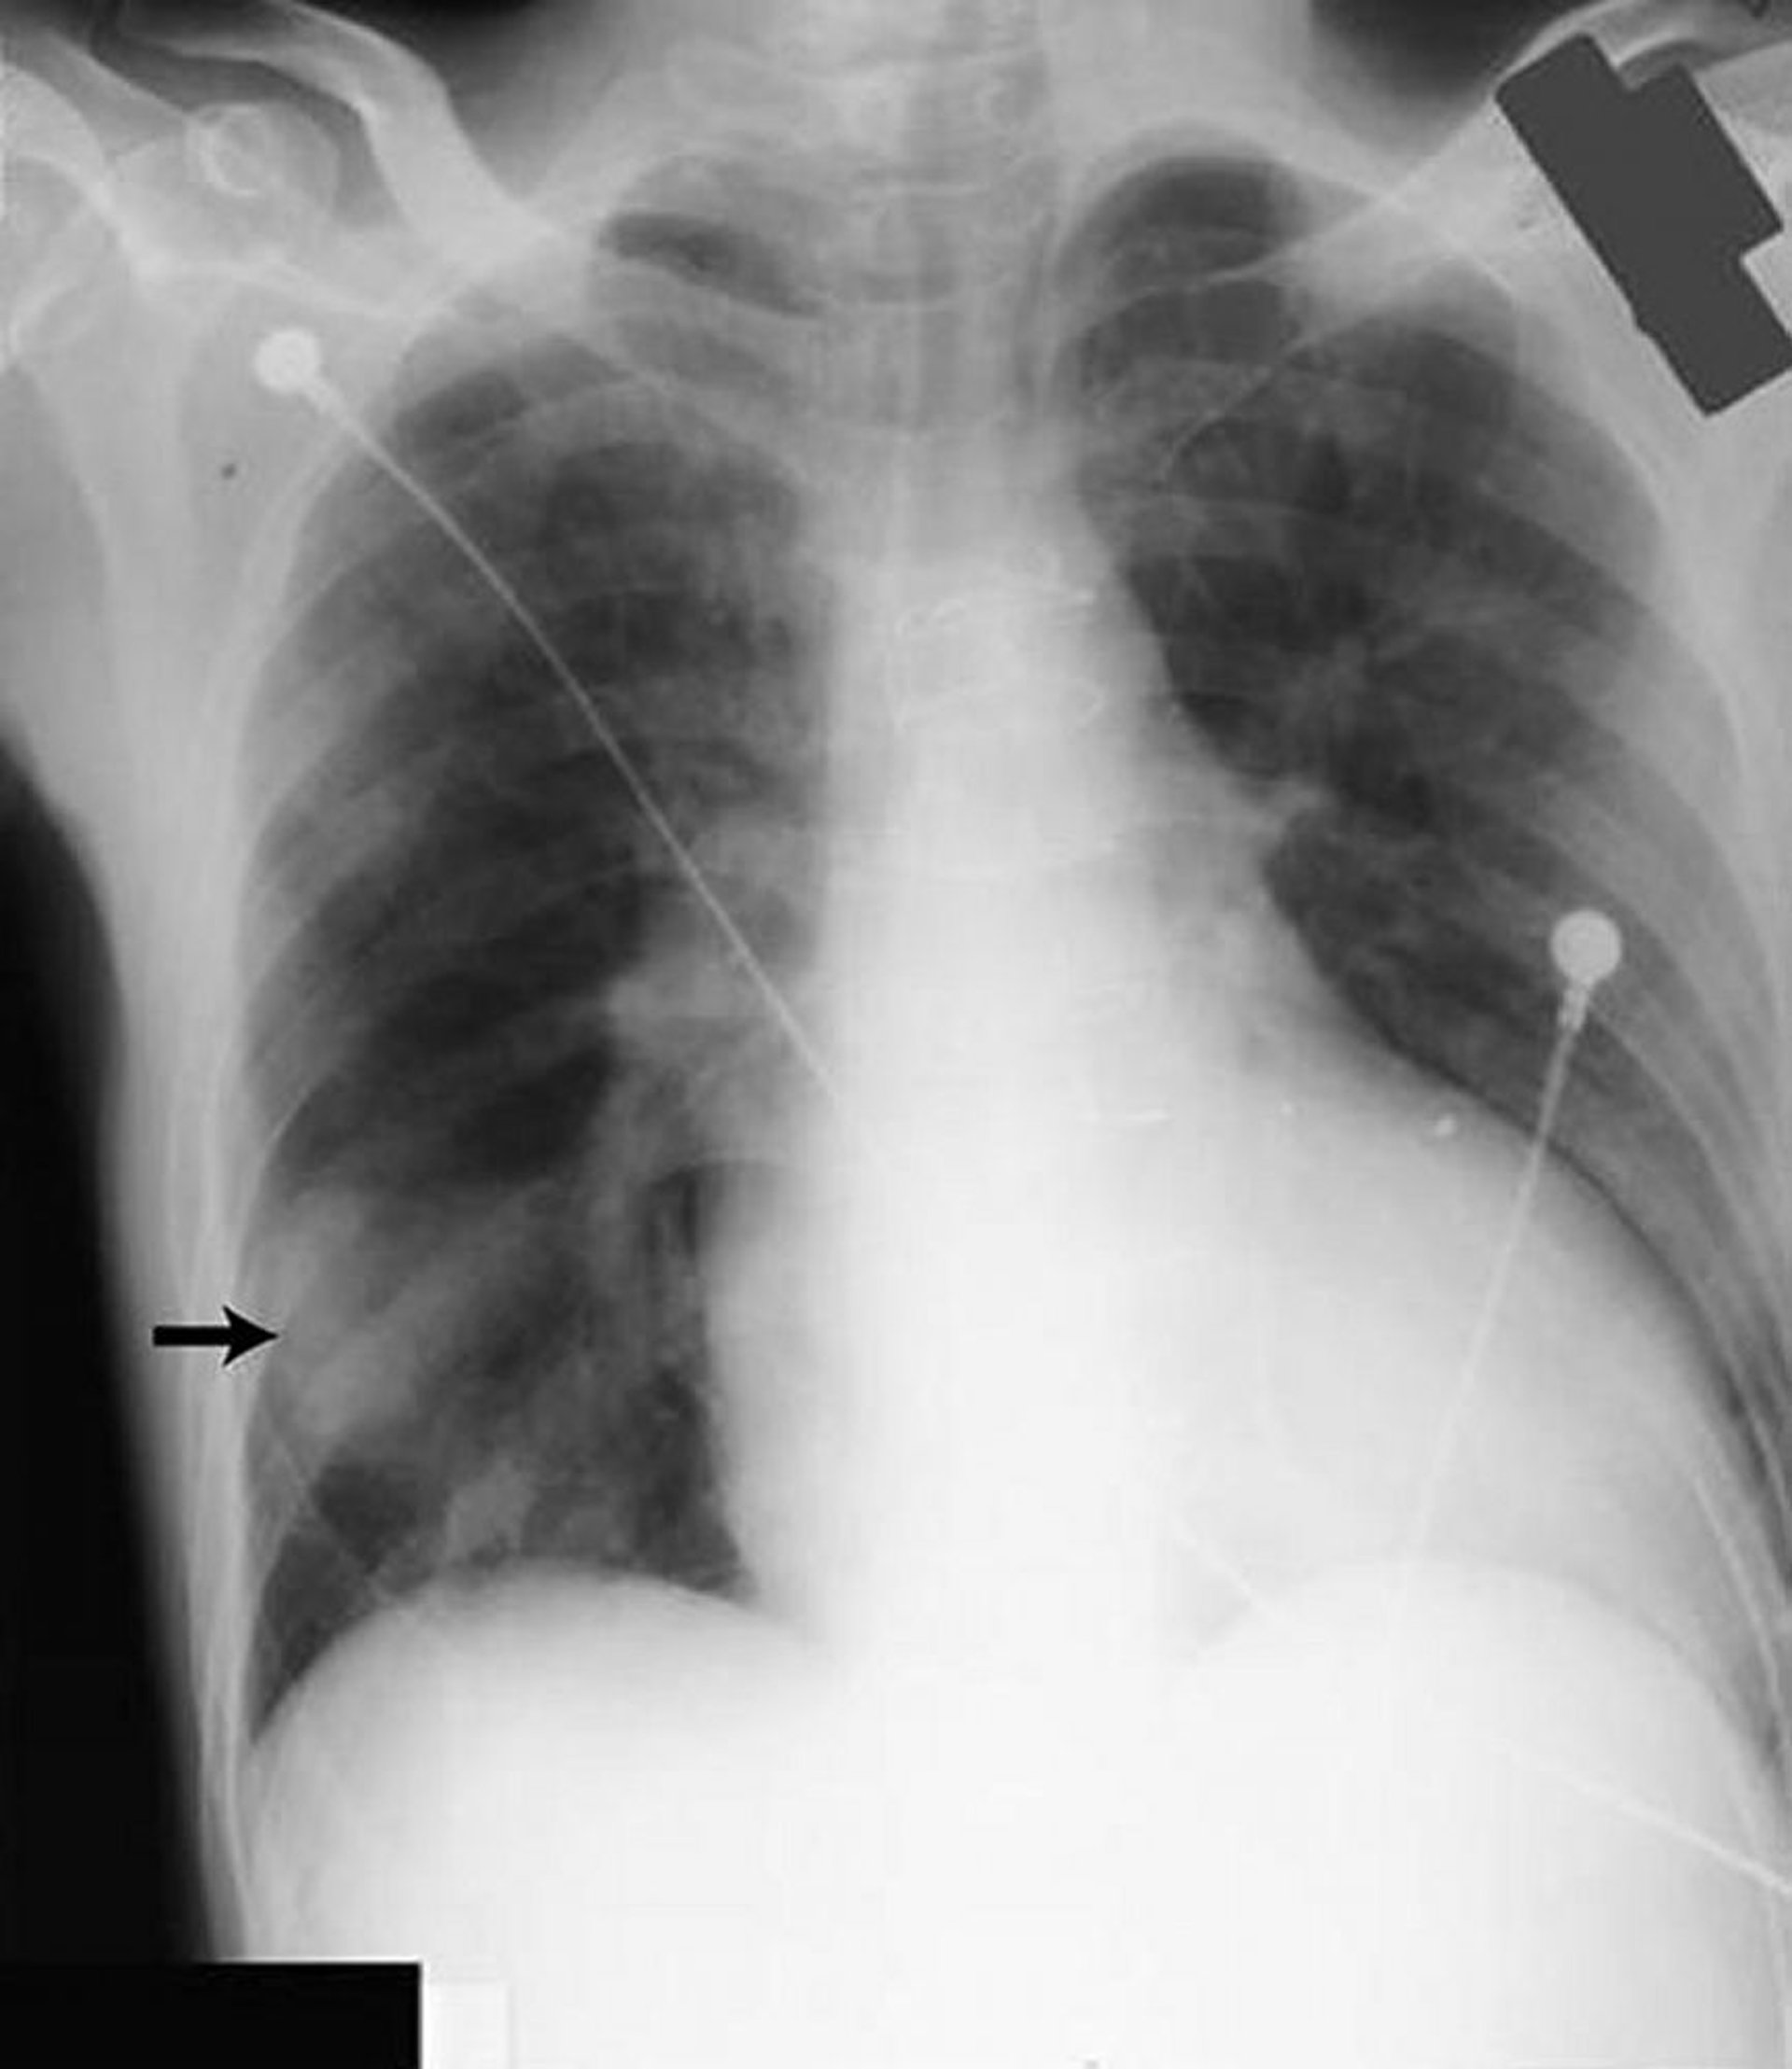

Затемнение в нижней части правого легкого (стрелка) напоминает плотную опухоль, но образовано жидкостью, скопившейся в косой щели у пациента с сердечной недостаточностью.

By permission of the publisher. From Huggins J, Sahn S. In Bone's Atlas of Pulmonary and Critical Care Medicine. Edited by J Crapo. Philadelphia, Current Medicine, 2005.